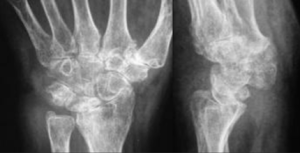

Pyrocarbon Wrist Replacement

Pyrocarbon joint replacement surgery for end stage wrist arthritis is a good alternative to traditional total wrist arthroplasty or fusion.

This implant, called the Amandys, is a large pyrocarbon pebble that acts as a “spacer” device to maintain wrist joint height and soft-tissue tension, thereby preserving wrist motion and treating painful arthritis. Wrist motion can be relatively well preserved compared to fusion (see below).

A good alternative to wrist fusion, which prevents further wrist motion.